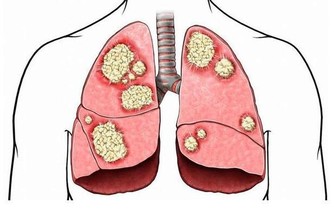

身體中的毒素,也可說是(污染物),多半是人體在吸收食品後,

進行新陳代謝中的產物,這就是『吃得多,病也多;吃得好,死得早』的道理,

它們往往停留在血管、肌肉、筋骨、關節以及臟腑的空隙中。

使肉體慢慢僵化、老化。注意:舉手時,要心無旁鶩,內心愈空愈好,愈靜愈好,